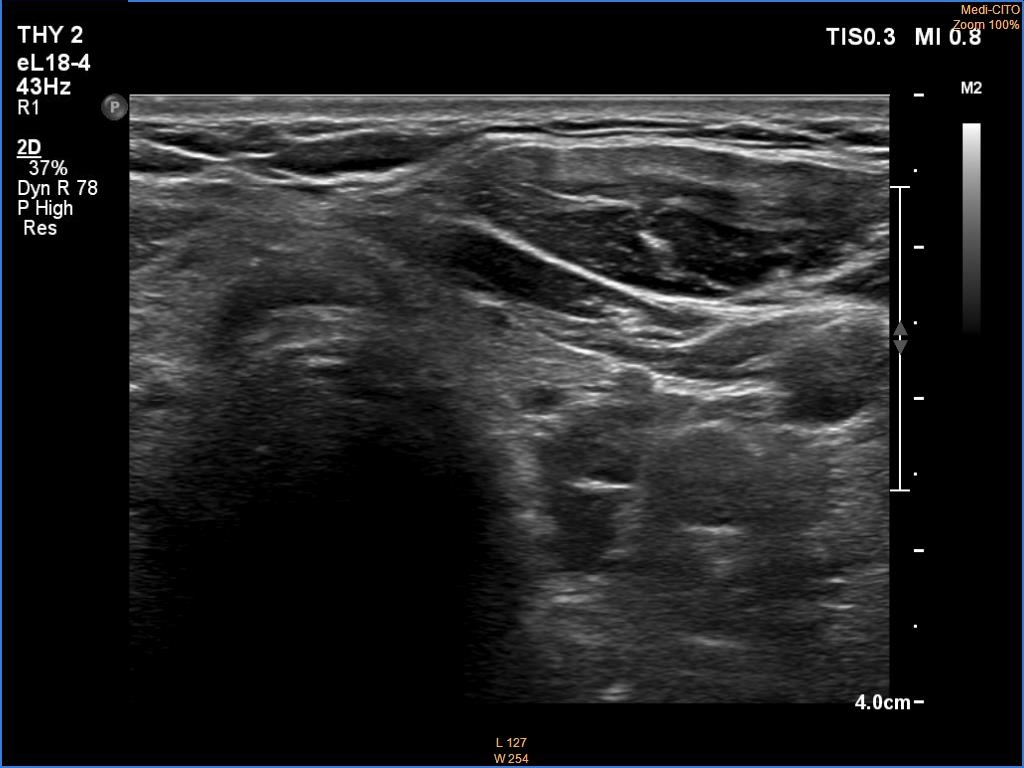

Ultrasonography. The thyroid was echonormal. There was a hypoechoic mass dorsal and under to the lower pole of the left thyroid lobe.